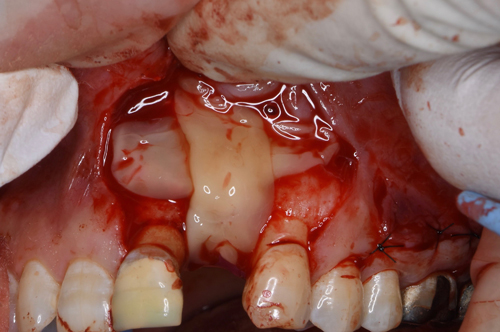

切開して開けてみると、2ヶ月前の抜歯跡が見受けられた。しかし

当院では骨の再生治療をインプラント移植時に同時進行で施しているので、全く問題はありません。

骨のない所に人工骨のβ–TCPを添加して、本物の骨に置換するのを待ちます。